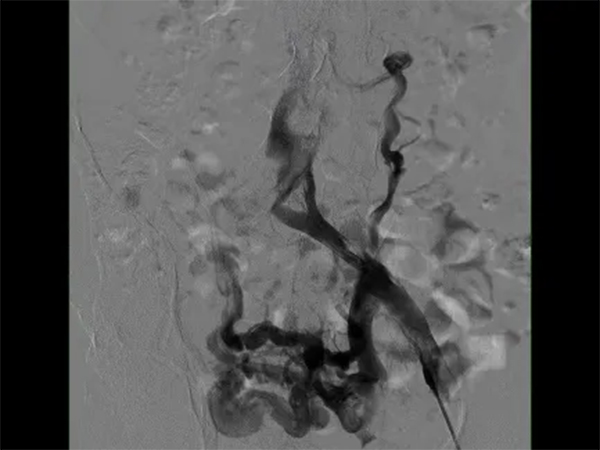

在與患者及家屬進行了詳細的交流后,患者決定住院治療。在經(jīng)過了詳細的病情分析后,介入科肖晉昌團隊為其制定了“髂靜脈造影+球囊擴張+支架置入”的治療計劃。術(shù)中造影發(fā)現(xiàn)患者左髂總靜脈近心端重度狹窄,周圍側(cè)支開放,狹窄兩端壓差明顯,均提示患者存在重度的髂靜脈壓迫(圖3)。予以球囊擴張狹窄處(圖4),然后行支架置入(圖5)。支架置入后造影患者左髂靜脈血液回流明顯改善,周圍側(cè)支減少。術(shù)后由張科醫(yī)師負責對其隨訪,經(jīng)過1個月的隨訪,患者目前下肢潰瘍基本愈合(圖6)。

圖3左髂靜脈造影